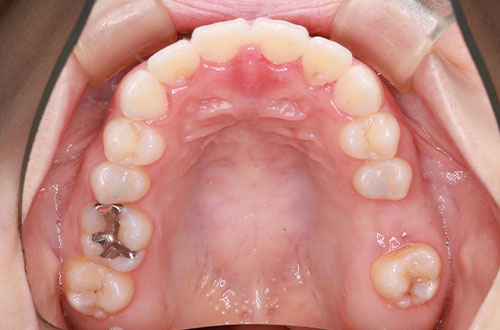

「前歯の部分矯正」~気になる部分だけ治療したい方向け

部分矯正とはその名の通り、「部分的に」歯並びを整える矯正になります。

矯正治療とは、金属製のワイヤーやブラケットを用いた矯正装置や、マウスピース型カスタムメイド矯正装置などを歯に装着して、乱れた歯並びや噛み合わせをキレイに改善する治療のことです。凸凹な歯並びや出っ歯、受け口、口元の突出などの噛み合わせの悪い歯並びを治します。